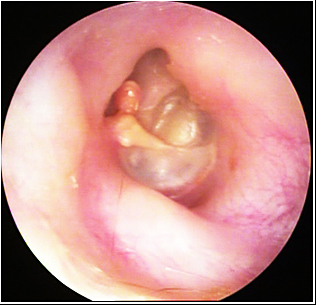

JFC Colesteatoma retrotimpánico.